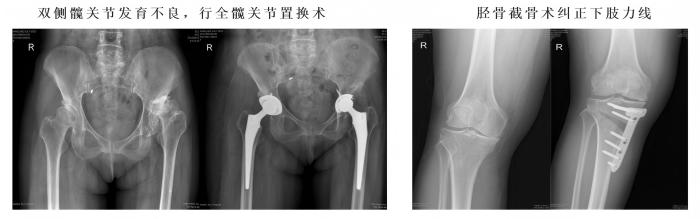

1、常规完成复杂全髋、膝关节置换手术(水泥型、生物型)、单髁置换手术、胫骨高位截骨手术、复杂保髋手术、股骨头坏死综合治疗、高龄老人髋部骨折综合治疗。

2、运动医学方面在我市率先开展膝关节镜下膝关节前交叉韧带撕脱骨折关节镜下复位线缆捆扎术、腘窝囊肿切除术、肩关节镜下肩袖损伤、肩关节撞击、髋关节撞击征修复治疗等国际最新技术。